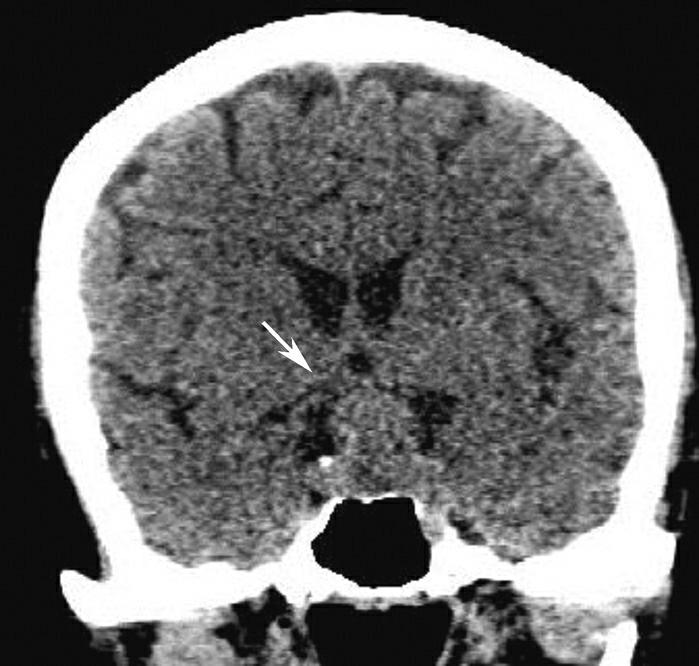

Alberta卒中项目早期CT评分(Alberta stroke program early CT score,ASPECTS)是一种评价急性缺血性卒中患者大脑中动脉供血区早期缺血性改变的简单、可靠、系统化的方法,是常用的脑卒中评定量表之一,可对缺血性病变快速进行半定量评价,有助于判定溶栓效果和远期预后。该评分主要基于CT平扫,具体分区如下(图1-2-76)所示,即选取大脑中动脉供血区2个层面。分区后共10个区域,每个区域记1分。评分时任何区域只要有低密度灶,则扣除该区域得分。正常脑ASPECTS评分为满分(10分),若MCA供血区广泛梗死累及全部区域时,则ASPECTS评分为0分。

图1-2-76 ASPECTS评分脑组织分区

A.在基底节层面(即丘脑和纹状体平面),分为各级分支M 1 、M 2 、M 3 、岛叶(缩写I)、豆状核(缩写L)、尾状核(缩写C)和内囊(缩写IC)后肢等7个区域;B.在基底节以上层面(基底节层面上2cm),包括M 4 、M 5 和M 6 。